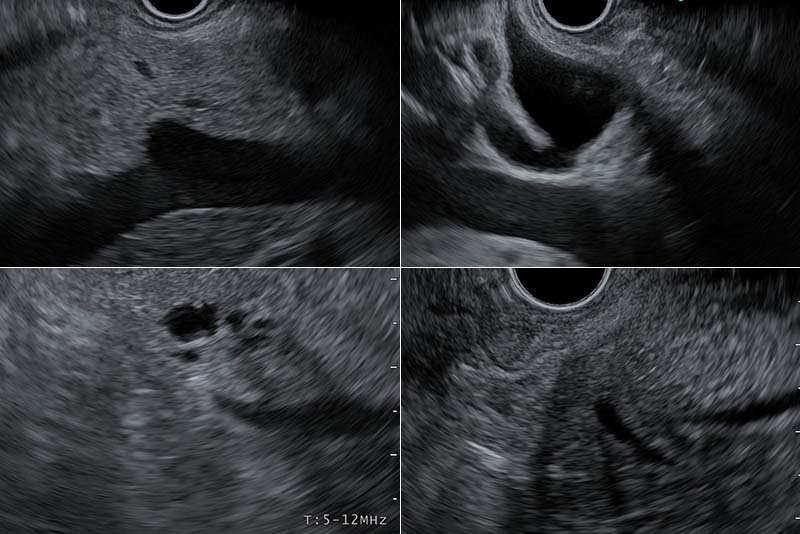

〈胃内操作による観察〉

脾静脈を描出し、静脈を追いかけるように観察します。自然とその上側に膵臓(体部と尾部)が描出され、観察可能となります。

脾門部まで観察できれば、膵尾部末端まで観察したことになります。一般に、腹部エコーではこの領域は描出不能と呼ばれる部位です。

〈十二指腸球部操作による観察〉

肝門部からVater乳頭まで観察します。特にこの領域は、胆管の観察に充填をおきます。

胆管を肝門方向に観察していくと、胆嚢管及び胆嚢の描出が可能となります。

〈十二指腸下行脚操作による観察〉

胆管と膵管の合流部であるVater乳頭を描出します。ここでは、膵頭部および、膵頭下部、膵こう部を観察することが可能です。